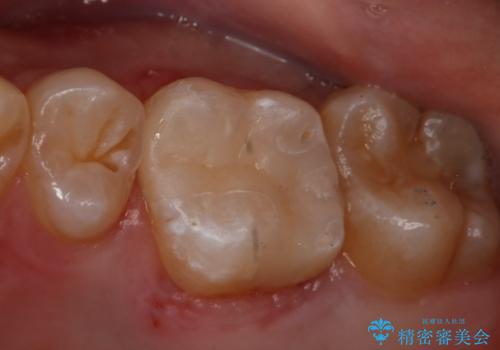

- 右上6番の銀歯をセラミックに変えたいと希望された患者様です。

切削量、形態を考慮し、セラミックインレーでの治療を計画しました。

銀歯と虫歯を除去した上でCRで裏層し形態を整えて印象を行っています。